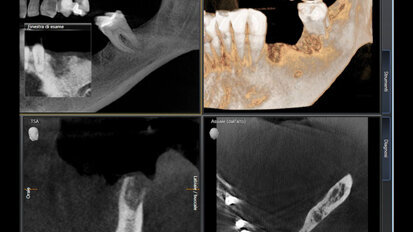

Rehabilitace Straumann